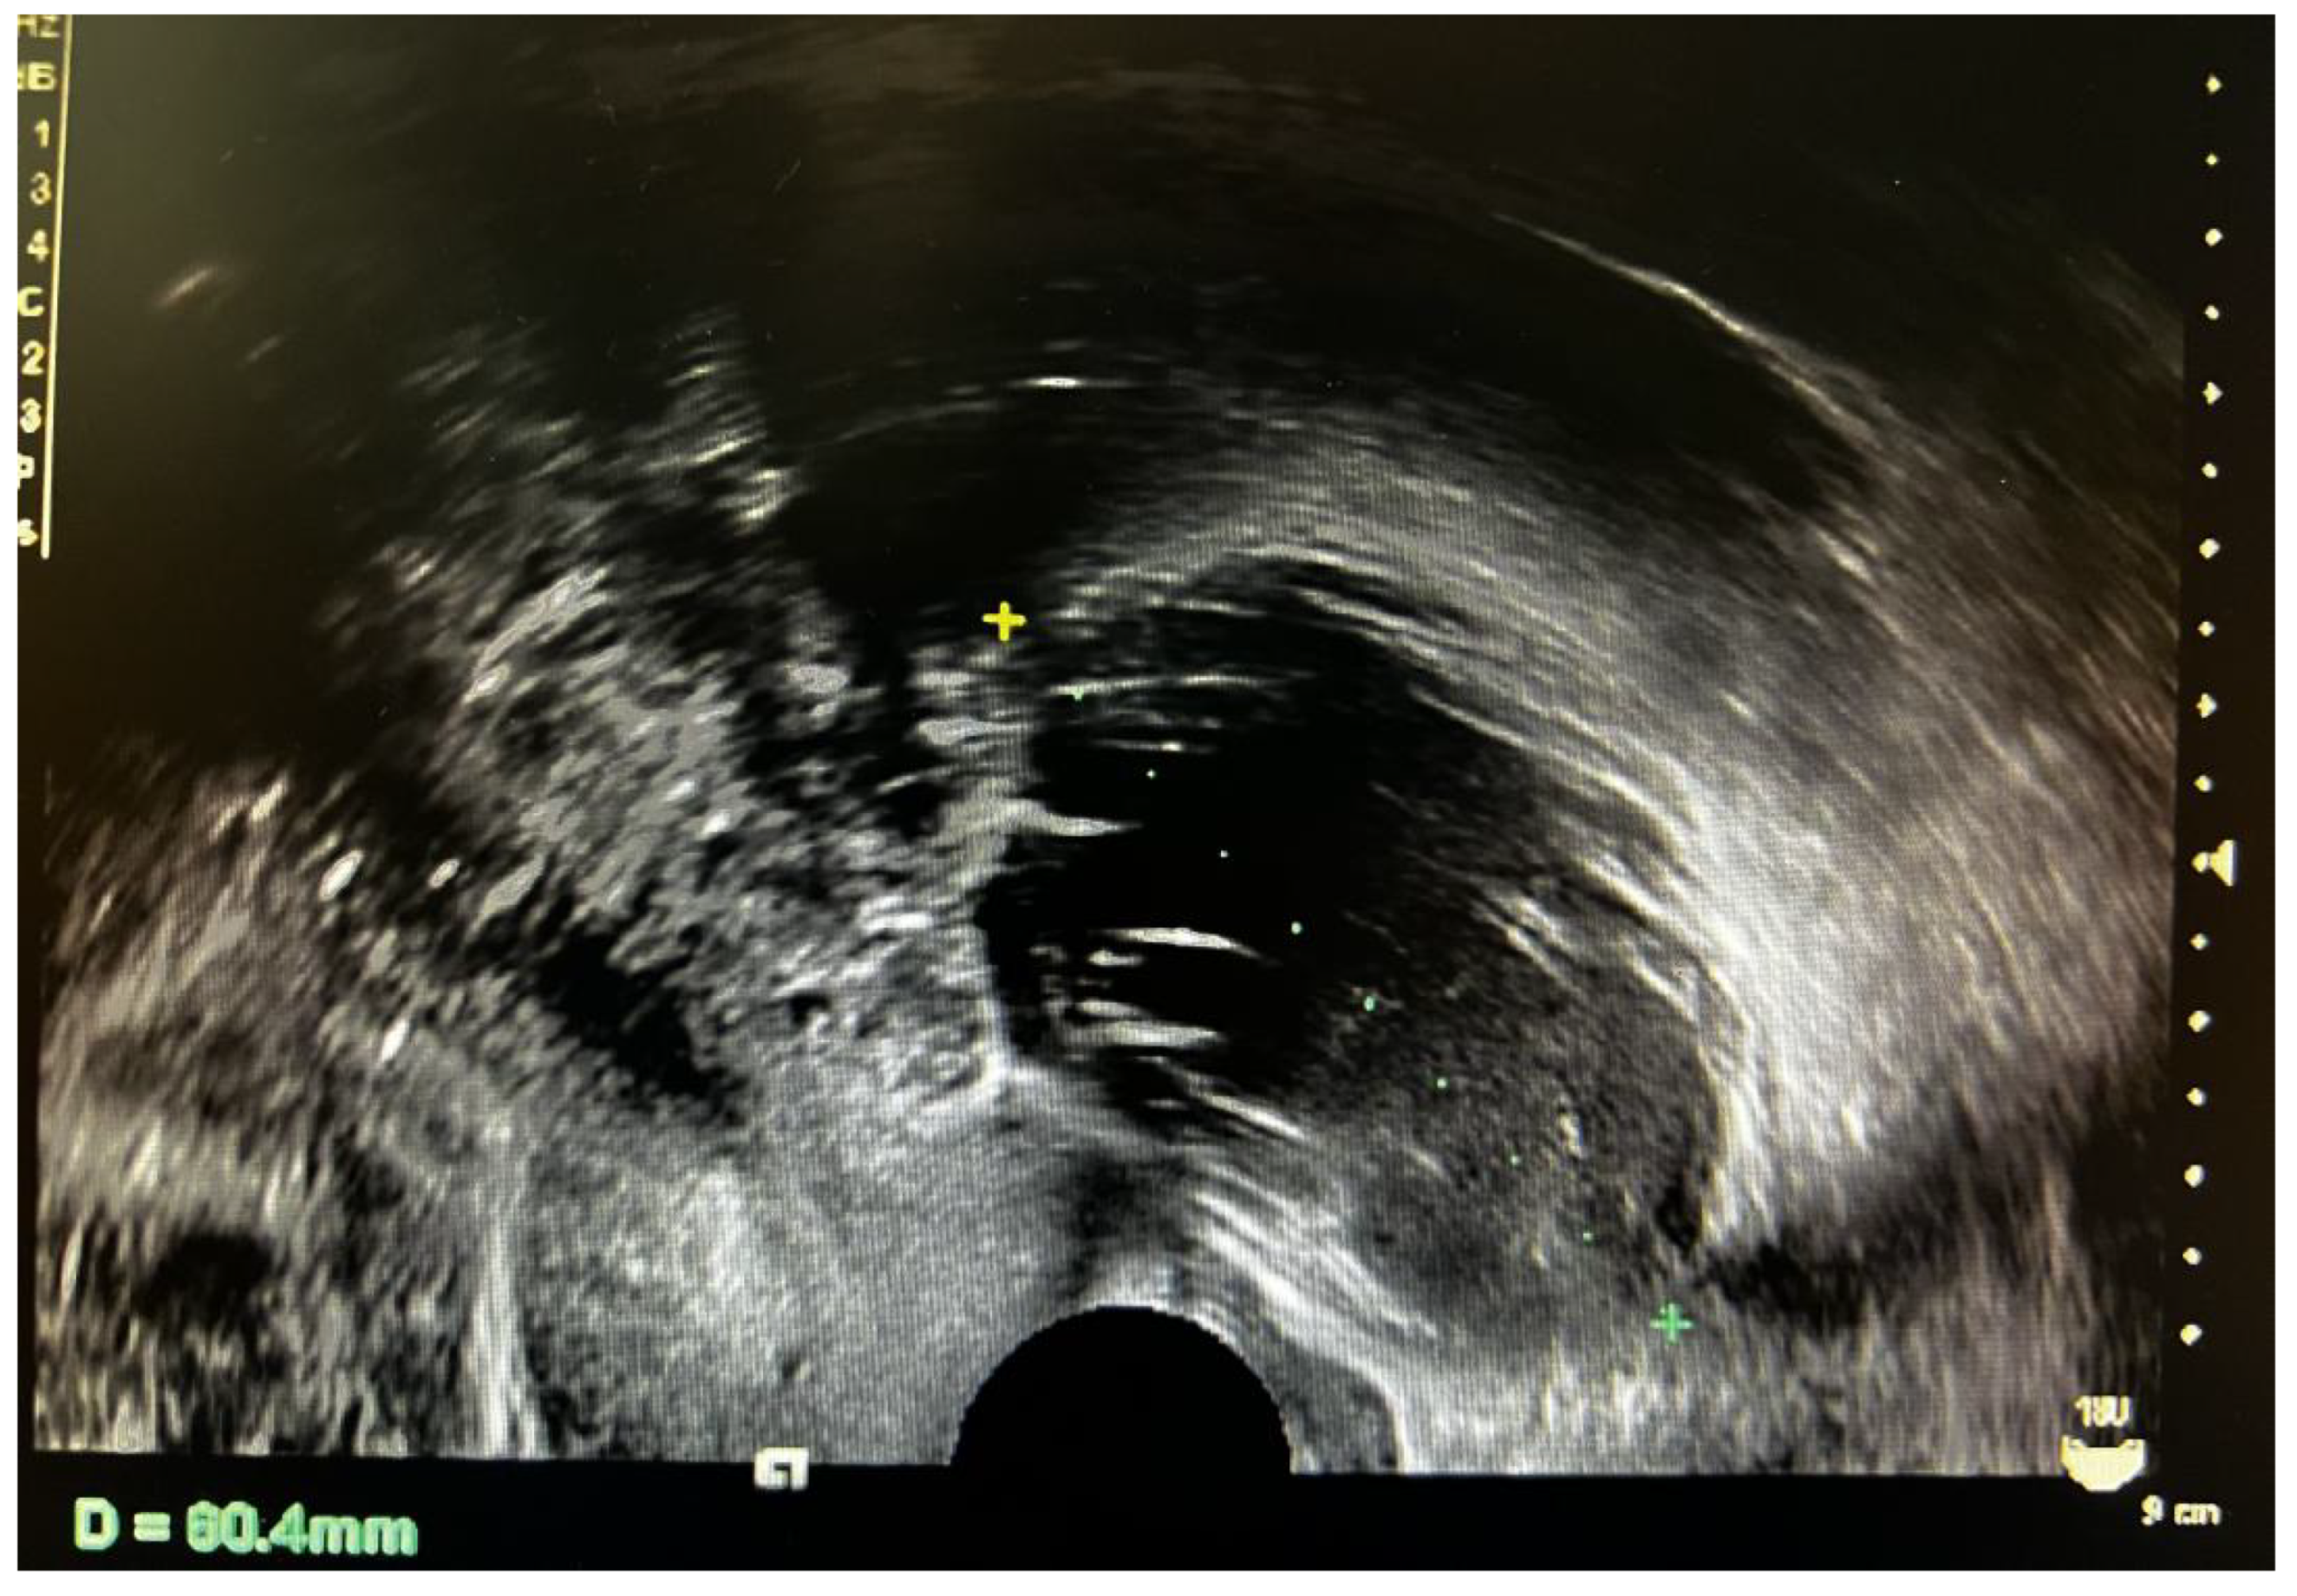

3.2. Imaging Characteristics